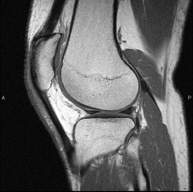

Exploración para el estudio de lesiones en la articulación, como roturas meniscales y de ligamentos cruzados (unicamente detectables mediante esta prueba), condropatía o desgaste del cartílago y multitud de otras alteraciones derivadas de la actividad deportiva y los cambios degenerativos (osteoartrosis). Tiene una duración aproximada de 18 minutos. No emplea radiación ionizante. - RM Pierna